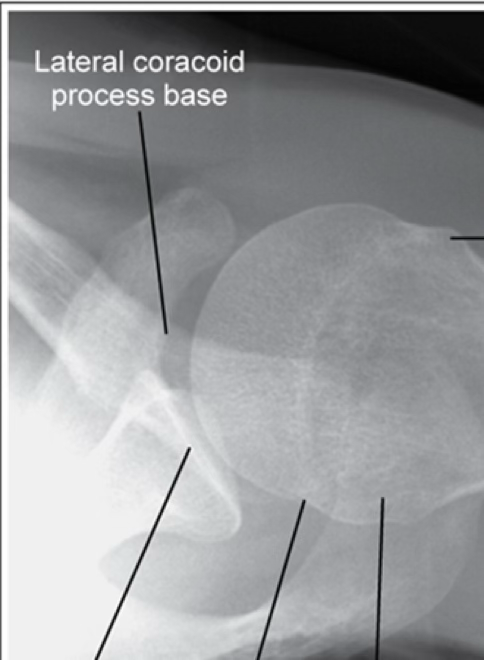

grashey

MCP tilt anteriorly

(coracoid process is below glenoid cavity)

MCP tilt posteriorly

(coracoid process above glenoid cavity)